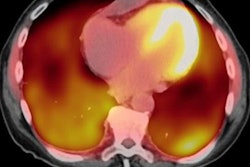

A handful of studies with small patient cohorts have evaluated PET/MRI in this regard. A December 2015 study by Hanneman et al found that when paired with MRI, PET achieved positive results for cardiac sarcoidosis for all eight patients (100%), compared with only four patients (50%) with PET/CT.

More recently, a January 2019 study of 10 patients by Wisenberg et al concluded that PET/MRI provided diagnostic-quality FDG images that were "at least equal to or better than those obtained with either the PET/CT scan, and subjectively crisper MR images" than those from a 1.5-tesla MRI scanner (J Nucl Cardiol, January 2, 2019).